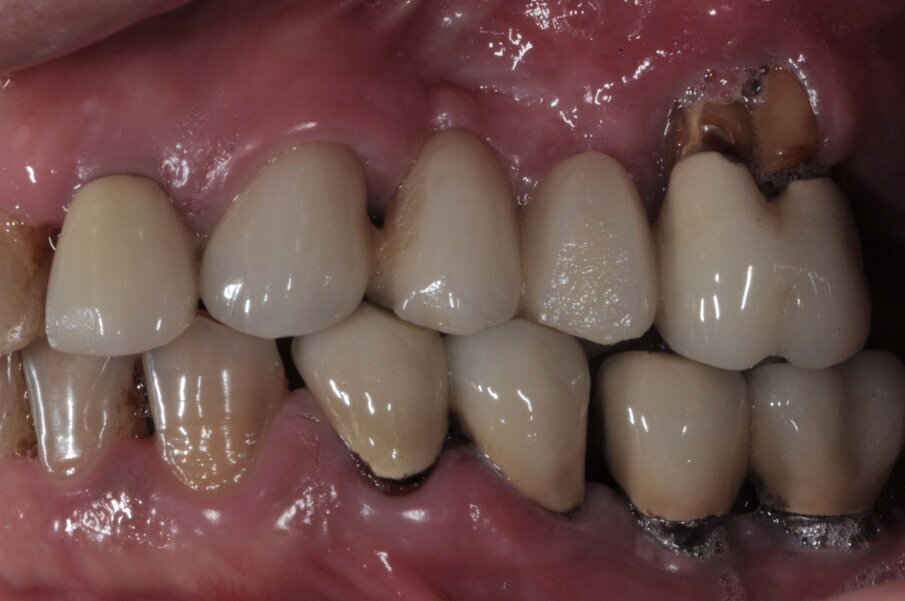

Il paziente di 50 anni in buono stato di salute, necessitava di una riabilitazione di tutta l’arcata superiore sia con impianti nei settori posteriori sia con corone sui denti frontali. Mentre nel sestante superiore destro era presente una quantità d’osso ideale per l’inserimento di impianti di diametro e lunghezza considerati standard, nel sestante sinistro era presente una quantità d’osso insufficiente sia verticalmente che orizzontalmente (Figg. 1-4). A causa dei timori del paziente sono stati esclusi interventi invasivi per incrementare i volumi ossei e si è deciso di inserire in posizione 24 un impianto BTI 3.0 3,3 x 10 mm e in posizione 26 un impianto BTI standard 3,7 x 5,5 mm con un minirialzo contestuale del seno mascellare.